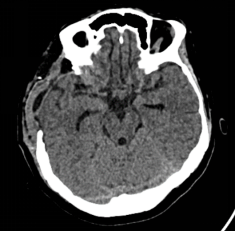

▲经过给患者“量身定制”的介入栓塞术治疗后,畸形血管团完全消失,正常的脑动脉及分支保留通畅

乘胜追击,刻不容缓!征得家属同意后,冯大勤立即带领神经外科脑血管病专业团队,在麻醉科、放射学科介入手术室等团队密切配合下,有条不紊地给叶女士完成了“全脑血管造影术”“球囊辅助下脑动静脉畸形栓塞术”和“支架辅助血管重建术”,在保留病灶周围正常血管结构的前提下成功栓塞了畸形血管团。手术一气呵成,体现了微创、高效、安全和个性化的理念与特点。术后经麻醉复苏,患者意识也恢复如初。